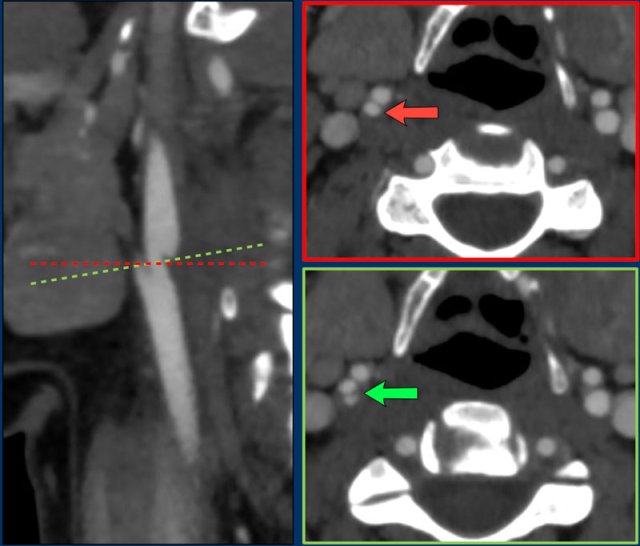

In this case the

carotid web is much smaller than in te previous example.

However, the imaging

criteria for the diagnosis of a carotid web still apply.

On the sagittal images

a self-like protrusion is seen on the dorsal aspect of the internal carotid

artery (arrow left image).

On the axial images the ridge of the carotid web

is seen connecting the lateral and medial wall of the internal carotid artery (arrow).

If you only look at the axial images,

you may miss a web.

The red arrow points at the ICA and

ECA, but no web is seen..

Only with by angulating the axial

plane perpendicular to the longitudinal axis of the ICA (green line and green

arrow) you will notice the web (ridge

connecting the lateral and medial wall of the ICA.

Of course the sagittal

reconstructions are superior for detecting a web.